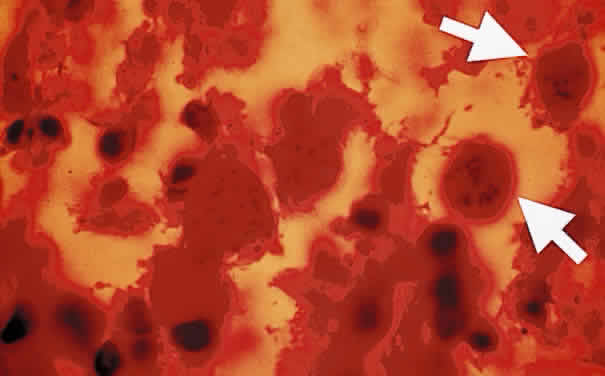

Bradyzoites are slowly metabolizing organisms found in cysts formed within the tissue of the infected host. The size of the Toxoplasma cyst varies, depending on the number of organisms that have multiplied within it. The cyst may reach more than 100 μm in diameter and may contain from 50 to 3000 organisms. The cyst wall is strongly argyrophilic and periodic acid-Schiff positive. It contains constituents that are derived from both the parasite and the host tissue. Constituent from the host tissue compose the outer part of the cyst, whereas those derived from the parasite are in the inner part of the cyst wall. Toxoplasmosis may be found in the inner layers of the retina after episodes of acute retinochoroiditis. The cyst may stay in the retinal tissue for years without showing any signs of invasiveness. Considering that the tissue cyst incorporates elements derived from the host into its outer wall, it is easily tolerated by the host, and no inflammatory reaction is seen around it (Fig. 2). It may remain for years in certain tissues, such as the eye or muscles, without provoking any inflammatory reactions. The bradyzoite inside the cyst derives its nutrition from the slow diffusion of substances through the cyst wall. The number of organisms increases within the cyst in the retina, and once the cyst wall breaks down by mechanical stretching, the bradyzoites escape, convert into tachyzoites, and invade contiguous cells. This process may lead to recurrence of retinitis. Certain immunologic mechanisms of the host may influence the organisms significantly. Immunosuppression coinciding with the rupture of the cyst and release of bradyzoites allows the organisms to become tachyzoites and proliferate in host tissue without restriction. The cyst of the Toxoplasma organism appears to be a defensive stage in its life cycle. The resistance of toxoplasmosis within chronically infected tissues of animals may lead to transmission of the disease by the ingestion of undercooked meat, including mutton, beef, pork, and chicken. Tissue cysts can develop within any organ and are commonly found in infected tissues of brain, eye, heart, skeletal muscles, and lymph nodes. Rupture of tissue cysts causes reactivation of the systemic toxoplasmosis in immune deficiency states, leading to dissemination of Toxoplasma organisms to other organs.

Fig. 2. Toxoplasma bradyzoites inside cysts of tissue sections in chronically infected rabbit's retina (arrows). The animal was killed 6 months after acute Toxoplasma retinochoroiditis after suprachoroidal injection of 1000 organisms (Beverley strain). There was no clinical evidence of inflammation at the time of killing. (H & E, × 400)